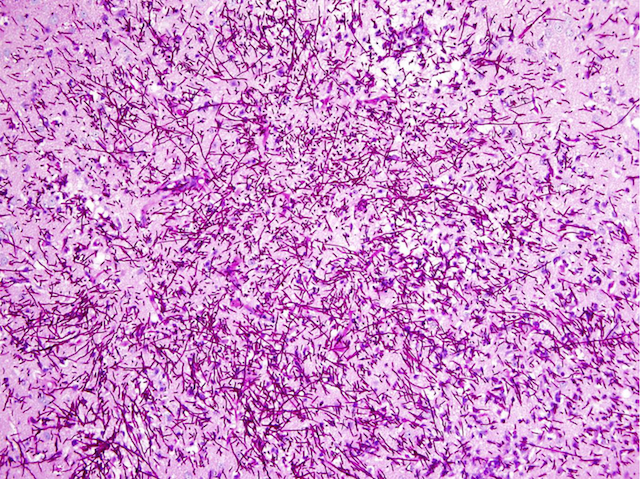

Brain Invasion

This is a snapshot of the inside of a mouse’s brain, seen here magnified 200 times down a microscope, and it’s not at all well. The dark pink speckles are threads of Candida fungus, invading the brain tissue and spreading aggressively. Candida is the most common fungal infection in humans, and can cause serious disease or even death. Anti-fungal drugs can help to keep infections in check, but they need to work alongside the patient’s own immune system. The reason the fungus is running riot in this mouse’s brain is because it’s missing a gene called Card9, which normally mobilises special infection-fighting cells, known as neutrophils, into action against the invaders. Babies born without the human version of the gene, CARD9, often get fungal infections affecting the brain, so figuring out how to boost their neutrophils or other parts of the immune system could prove to be a lifesaving solution.